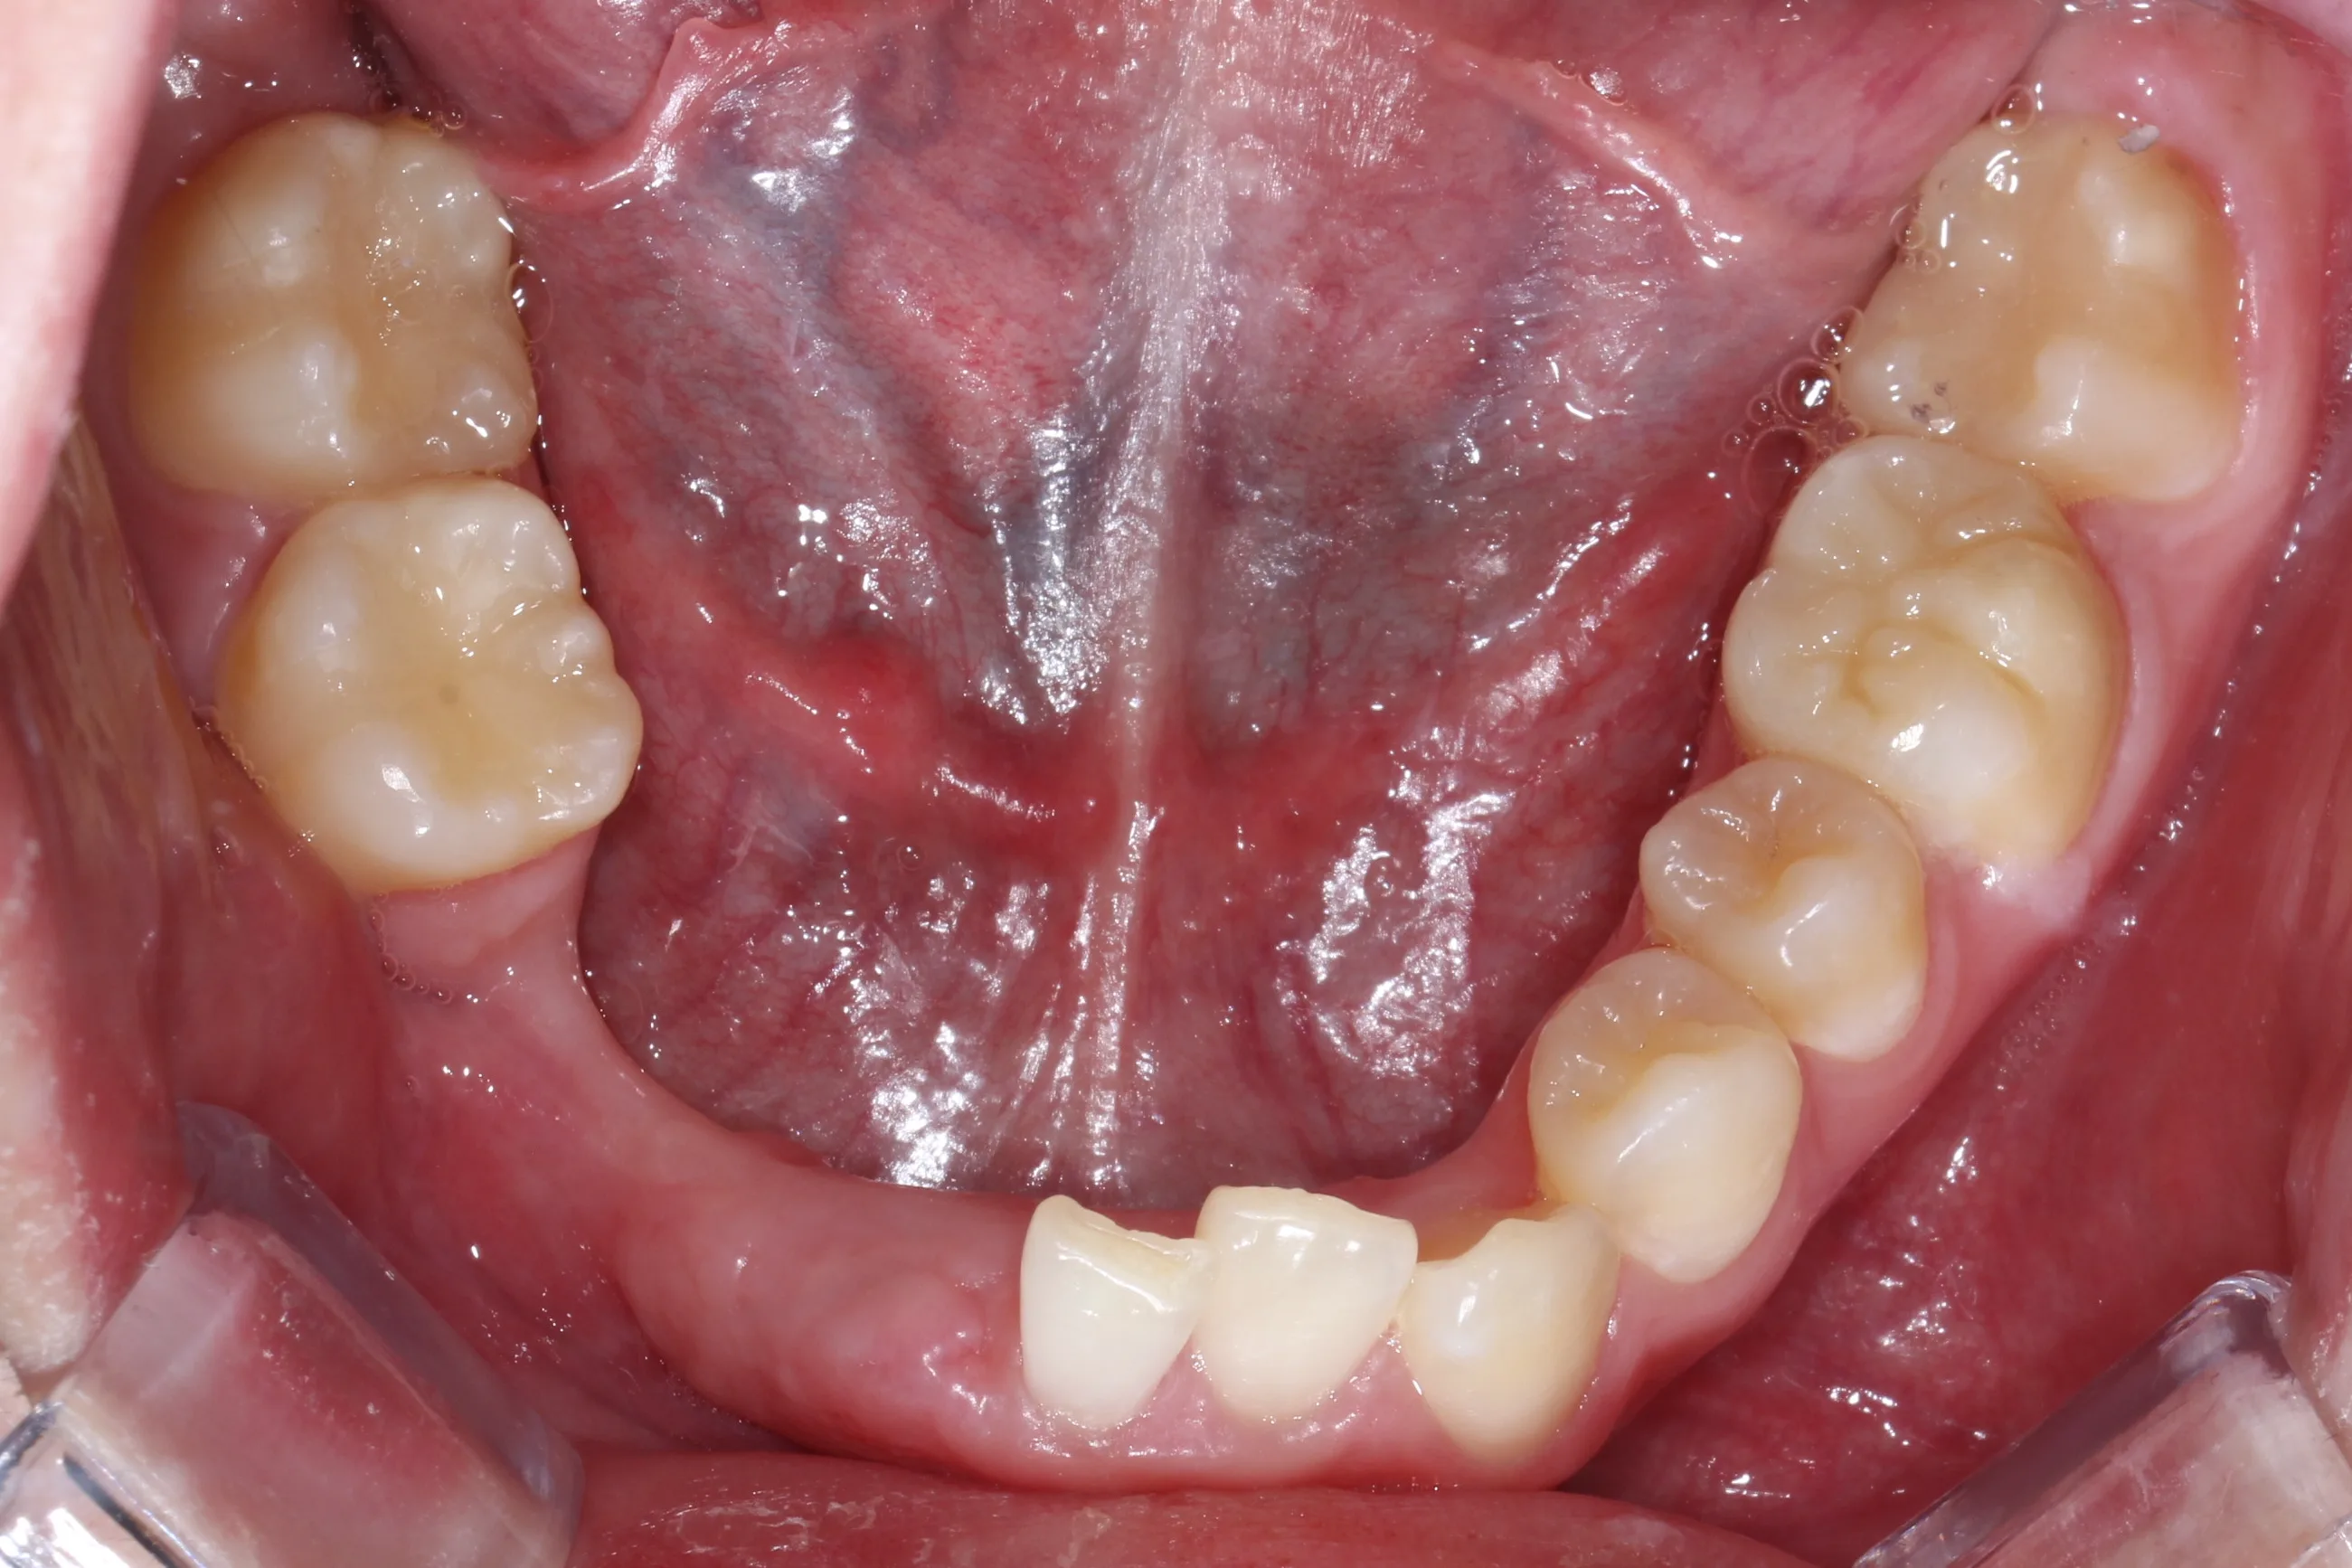

만 21세 환자로, 기존에 사고로 여러 치아를 다치고 상실한 상태로 매우 심한 교합무너짐이 있었습니다.

치료전 (Before)